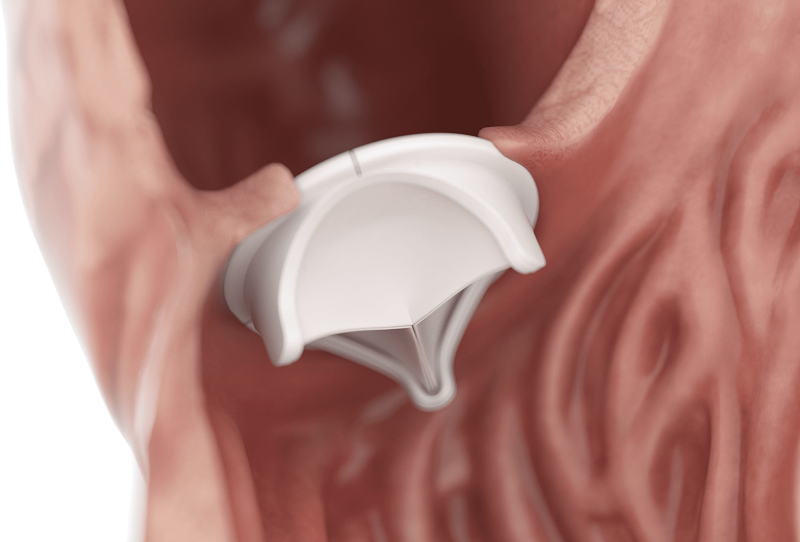

Valvular degeneration and Rheumatic heart valve disease are not so rare and Minimally Invasive Cardiac Surgery brings new age techniques and improved quality of life.